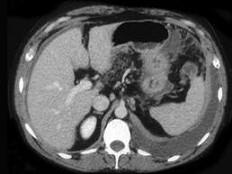

问题 女,36岁,低热、乏力,腹胀不适一月余,结合影像检查,应考虑为 ( )

选项 A.肝硬化腹水 B.结核性腹膜炎 C.腹腔转移瘤 D.心源性腹腔积液 E.急性化脓性腹膜炎

答案 B